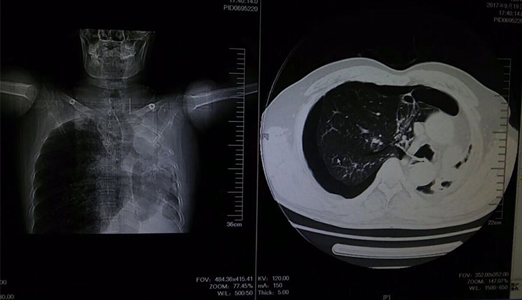

该患者为中年男性,胸闷,气促,休息后症状无缓解,来院就诊时全身大汗淋漓,口唇发紫,呼吸困难。临床医学院/附属医院医生询问病史后,发现该患者病情较复杂,且患者及家属对既往病史情况不太了解。考虑情况危急,当班医师立即组织抢救,给予吸氧、建立静脉通路及行胸部CT,同时请胸外科医师急会诊。经详细检查后,发现患者右肺自发性气胸,如不及时救治将危及生命。医务人员立即为患者做了右胸腔穿刺排气抢救,后给予胸腔闭式引流。在全体医护人员一个多小时的努力下,患者病情得到缓解,患者及家属对临床医学院/附属医院医务人员的精湛医术表示感谢。